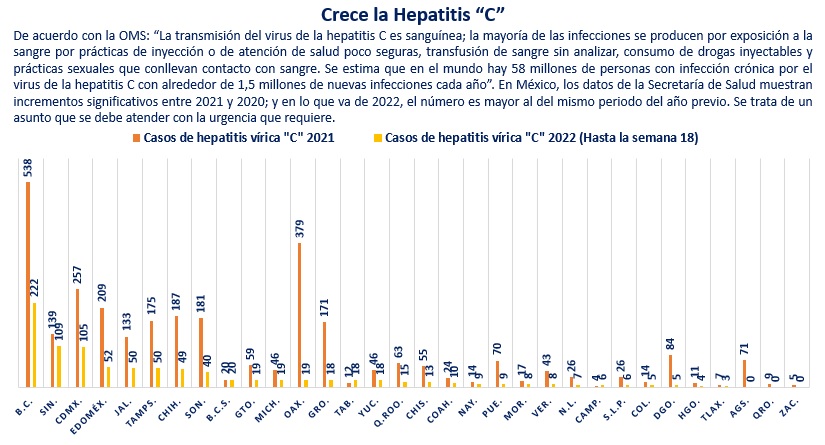

Respecto de la Hepatitis Vírica “C”, el acumulado hasta la semana 52 del 2020 fue de 1,400 casos; mientras que en el 2021 se legó a 3,095 casos confirmados, es decir, un incremento de 121%. Para la semana 18 del 2022, la cifra es de 916 casos, es decir, 2% superior a los 898 casos registrados en el mismo periodo del 2021.